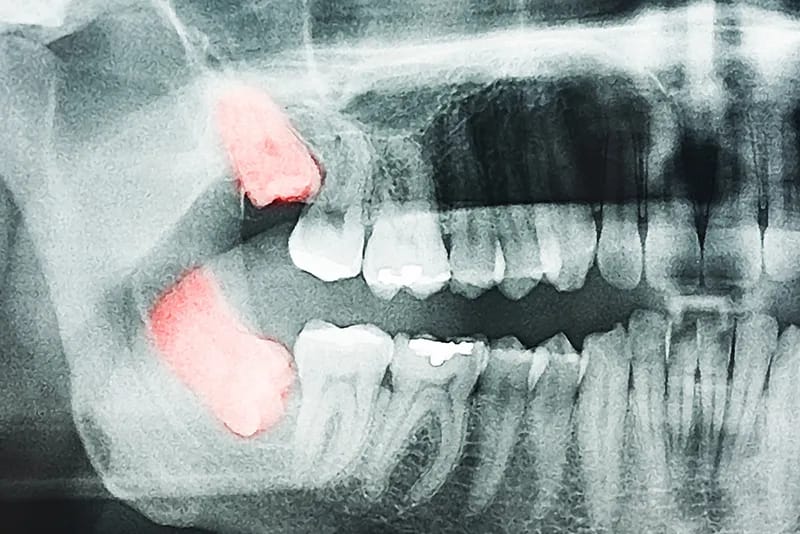

Denti del giudizio o canini inclusi

I denti del giudizio spesso richiedono controllo perché possono trovarsi in posizioni inadeguate: inclusi (non hanno spazio per erompere e possono spingere gli altri denti) o semi‑inclusi (emergono solo parzialmente).

L'estrazione dei denti del giudizio è un intervento comune. Prima vengono gestiti, minore è il rischio di complicanze. Raccomandiamo pertanto di verificarne la posizione già in adolescenza e di prevederne il decorso. Un controllo almeno annuale è consigliato.